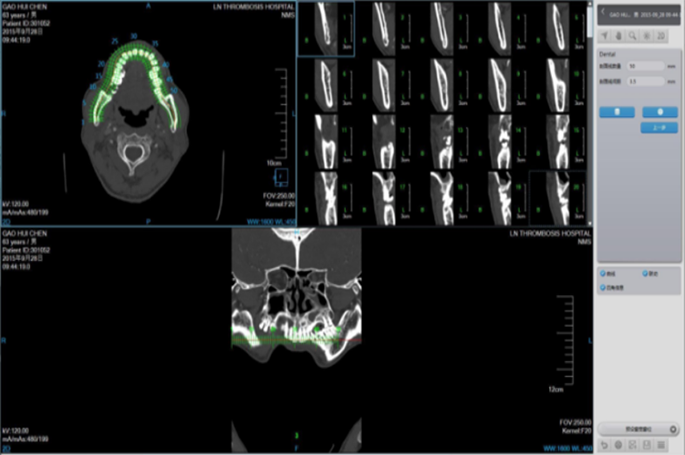

Cardiac Application Images

Coronary Calcium Scoring

Estimate the amount of calcium in the coronary arteries

• Agatston score

• Volume score

• ROI information calculation

Cardiac Viewer Images

View heart images of each phase, execute three-dimensional reconstruction and heart extracted for CT heart images, and then view patient heart by more intuitive way, diagnosis various cardiovascular diseases.

• Different phases data comparison

• 4D play

• Oblique MPR display